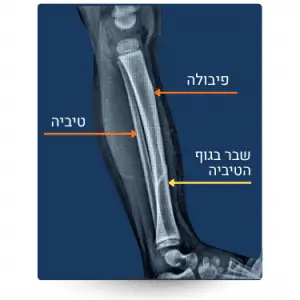

השוק שהינו החלק שבין הקרסול והברך מורכב משתי עצמות: עצם השוק (טיביה) ועצם השוקית (פיבולה).

שברים בעצמות השוק בכלל ובטיביה בפרט עלולים להיגרם כתוצאה מפגיעה בתאונת דרכים כהולך רגל, או כתוצאה מתאונה של רוכבי אופנוע.